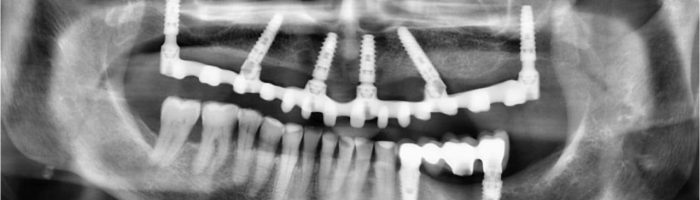

La cirugía bucal en Valencia también incluye procedimientos como la cirugía de la encía para la estética de la sonrisa, los implantes dentales y la cirugía regenerativa ósea o reconstructiva en casos de falta de hueso para permitir la posterior colocación de implantes dentales.

La cirugía ósea regenerativa e implantológica es otro tipo de cirugía bucal. Este tipo de cirugía se realiza cuando el paciente tiene atrofia ósea o falta de hueso, para posteriormente poder colocar implantes dentales.